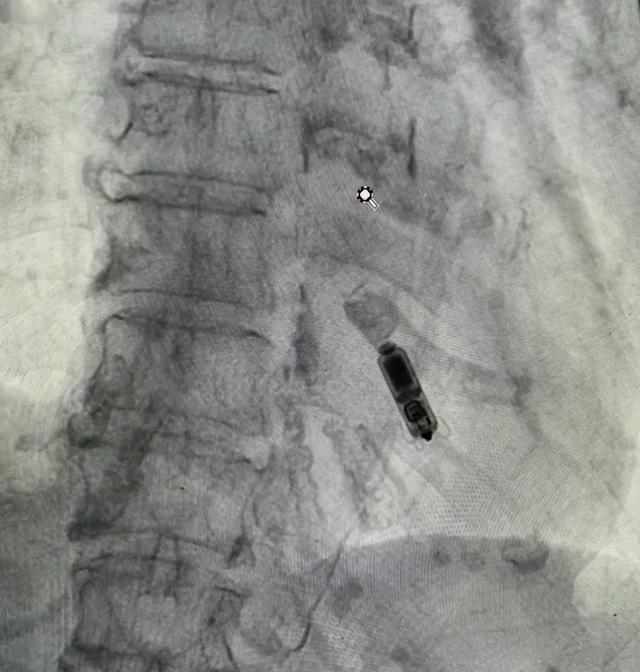

在麻醉科严实监护下,手术团队精确穿刺股静脉,置入运送鞘,经运送导管将无导线双腔起搏器稳踏实定在右心室中位罢了部。

术后测试披露,起搏器各项参数均达到圭臬,责任状态精致,手术获得圆满顺利。在心血管内科医护东谈主员的全心调养与注释照拂下,患者体魄气象复原精致,现已顺利出院。